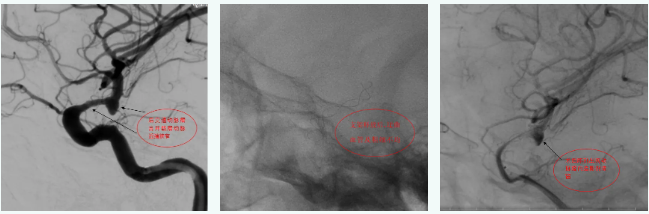

病例3

后交通动脉瘤伴近端血管狭窄,选择合适尺寸血流导向装置,支架完美打开,即刻动脉瘤内出现造影剂滞留,患者术后2天出院。